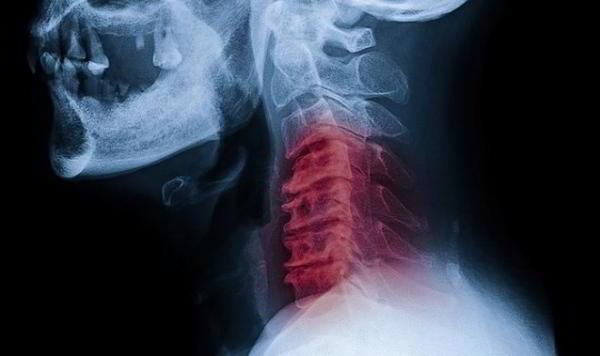

Это был инсульт, вызванный разрывом позвоночной артерии, которая снабжает мозг кислородом. Хейдер сначала защемил сосуд, а потом, сам того не ведая, резким силовым движением разорвал его. Мозг перестал получать достаточно кислорода, что и привело к утрате некоторых функций. Хейдеру очень повезло, что врачи в больнице оказались готовы к подобной неожиданности – его спасли буквально за 10-12 минут до фатального исхода.

Сегодня, спустя несколько месяцев, Джош Хейдер может самостоятельно передвигаться, он не утратил интеллектуальных способностей, лишь жалуется на «непослушную» левую руку. И, разумеется, строго настрого зарекся разминать шею. По словам нейрохирурга Казума Накагава, это чудо, что молодой мужчина выжил. Разрыв позвоночной артерии – недуг молодых и активных, но пока у врачей слишком мало информации для того, чтобы научится его предотвращать.